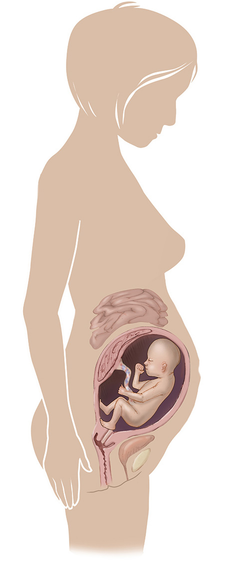

مراحل تطور الجنين أثناء الحمل

تطور الجنين خلال فترة الحمل على ثلاثة مراحل: أول 14 أسبوع من الحمل ، ثم تطوره بداية من الأسبوع 14 وحتى 28 أسبوعا ، ثم الثلث الأخير من 28 إلى 40 أسبوع من الحمل ... المزيد

مراحل تطور الحمل أسبوعيا بالصور

مراحل تطور الحمل أسبوعيا لكل من الأم والجنين داخل الرحم مدعومة بالصور التوضيحية ... المزيد